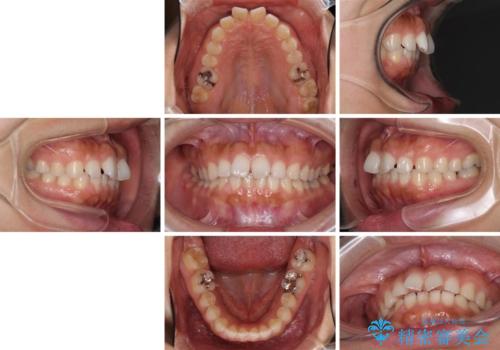

隙間の空いた前歯を閉じたい インビザライン矯正

- 30代女性

- インビザライン

- 4年10ヶ月

- 前歯の隙間を気にして来院された患者様です。

隙間、捻転ともに軽微でありましたが、下顎前歯の突き上げにより隙間ができていたため、インビザラインを用いて咬み合わせを改善しながら前歯の歯列を整えていくこととしました。

当初は1年程度で終えられると思いましたが、治療途中から装着時間が短くなったり、来院間隔が長期になったりとし、結果として4年半以上の治療期間となりました。

治療途中に上顎前歯は失活してしまいましたが、変色が顕著ではないため、経過を見ていくこととなりました。